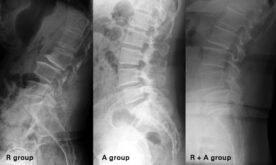

Minor retrolisthesis in 2021

Minor retrolisthesis image This image shows minor retrolisthesis.